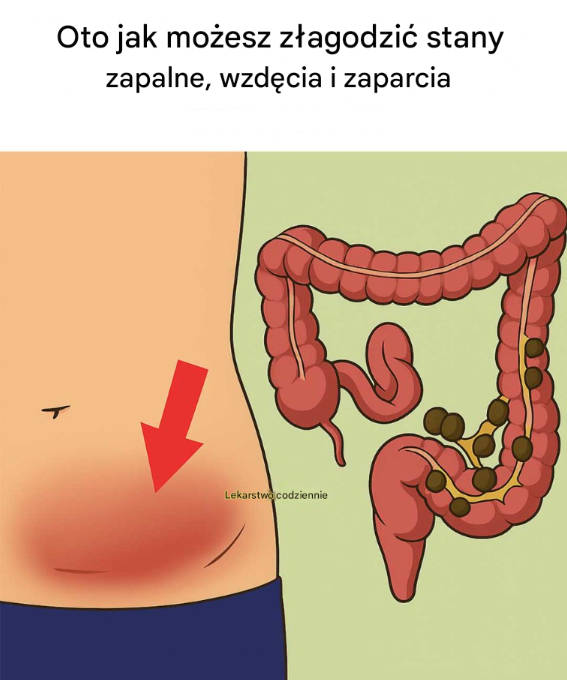

Szkoda, że nie zobaczyłem tego wcześniej! Stany zapalne, wzdęcia i zaparcia to częste problemy trawienne, które mogą znacząco wpływać na jakość życia. Stany…